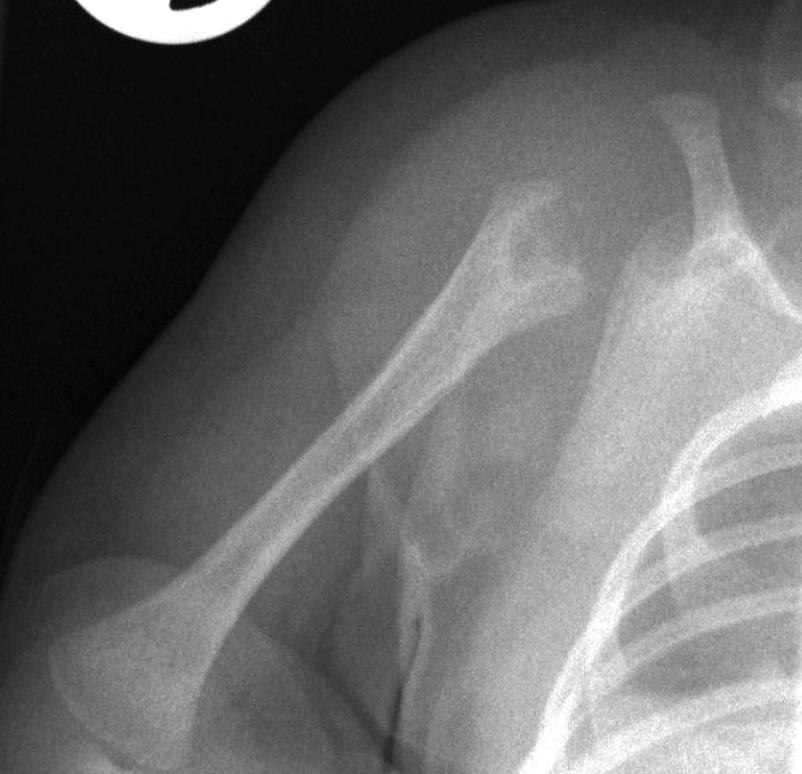

Image

37.a.

37.b.

37.c.

37.d.

37. a-d) X-ray of the right humerus. a. Rarefaction in the proximal-medial part of metaphysis of the right humerus – early osteomyelitis. b. Two weeks after the lytic area has grown. c. 1 month later sclerotic regeneration has begun. d. 4 months after almost complete healing. Osteomyelitis, infant.